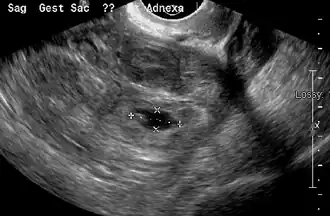

Transvaginal ultrasonography

An ultrasound showing a gestational sac with the fetal heart in the fallopian tube has a very high specificity for ectopic pregnancy. It involves a long, thin transducer, covered with the conducting gel and a plastic/latex sheath and inserted into the vagina.[38] Transvaginal ultrasonography has a sensitivity of at least 90% for ectopic pregnancy.[5] The diagnostic ultrasonographic finding in ectopic pregnancy is an adnexal mass that moves separately from the ovary. In around 60% of cases, it is an inhomogeneous or a noncystic adnexal mass, sometimes known as the "blob sign". It is generally spherical, but a more tubular appearance may be seen in the case of hematosalpinx. This sign has been estimated to have a sensitivity of 84% and a specificity of 99% in diagnosing ectopic pregnancy.[5] In the study estimating these values, the blob sign had a positive predictive value of 96% and a negative predictive value of 95%.[5] The visualization of an empty extrauterine gestational sac is sometimes known as the "bagel sign", and is present in around 20% of cases.[5] In another 20% of cases, there is visualization of a gestational sac containing a yolk sac or an embryo.[5] Ectopic pregnancies where there is visualization of cardiac activity are sometimes termed "viable ectopic".[5]

A pregnancy not in the uterus[39]